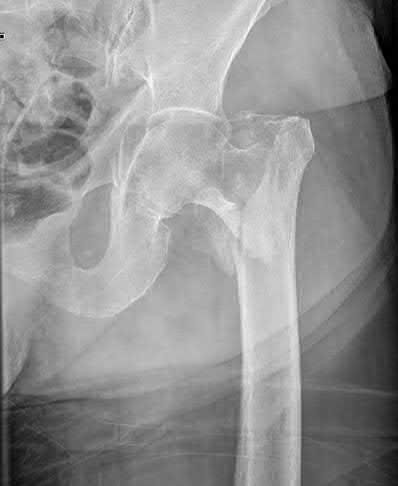

Question 2:

A 28-year-old male sustains a severe hyper-dorsiflexion injury to his ankle in a motor vehicle accident, resulting in a Hawkins Type III talar neck fracture. Which of the following arteries provides the predominant blood supply to the body of the talus, placing it at significant risk for avascular necrosis in this injury?

The artery of the tarsal canal, which is a branch of the posterior tibial artery, provides the dominant blood supply to the talar body. In a Hawkins Type III fracture (talar neck fracture with subtalar and tibiotalar dislocation), the blood supply from the artery of the tarsal canal, the artery of the sinus tarsi, and capsular vessels are disrupted, leading to an avascular necrosis (AVN) rate approaching 100%.